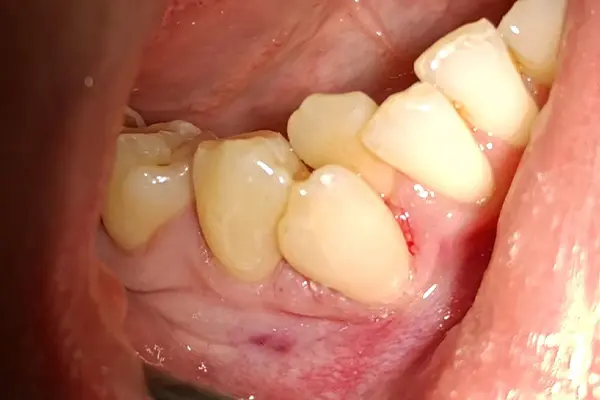

Виталий Лаврысь: “43, 44 зубы, кариес дентина, вестибулярная полость”

В этом клиническом случаем от Виталия Семёновича Лаврысь мы рассмотрим лечение кариеса дентина 43 и 44 зуба с использованием композитов B&E.

На первом фото - сразу после полировки, на втором через два дня.